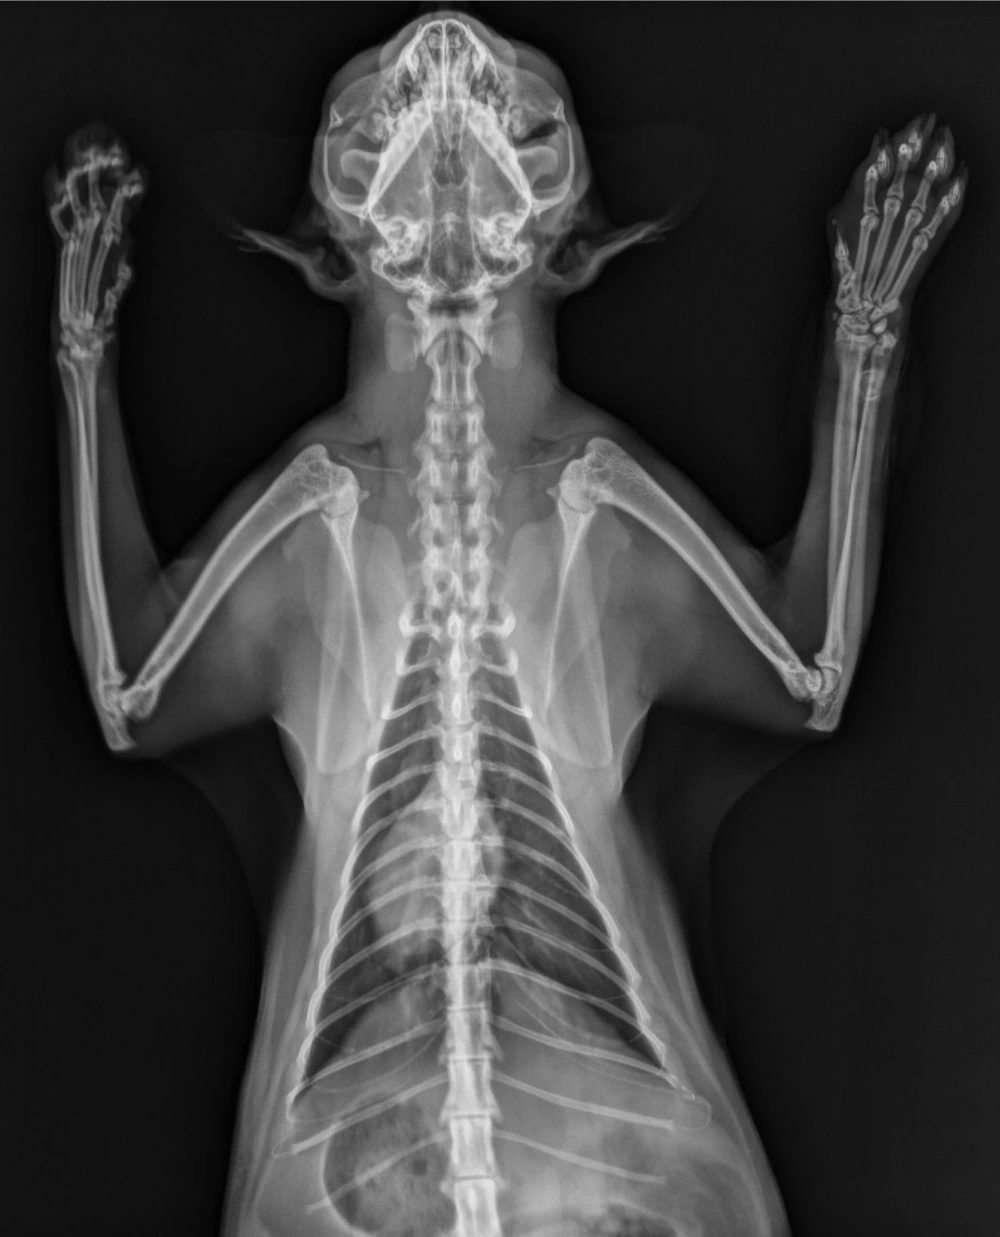

Radiografia tórax cachorro

Biota Centro de Diagnóstico Veterinário: Especialista em radiografia tórax cachorro

A radiografia tórax cachorro é um exame fundamental para avaliar a saúde pulmonar e cardíaca dos animais.

Essa técnica de diagnóstico por imagem permite identificar possíveis problemas respiratórios, doenças cardíacas, lesões e outras condições que podem afetar o sistema respiratório do seu pet.

Para realizar a radiografia tórax cachorro, o animal é posicionado de maneira adequada para obter imagens nítidas dos pulmões, coração e demais estruturas torácicas.

O procedimento é rápido, indolor e não invasivo, sendo essencial para auxiliar médicos veterinários a diagnosticar doenças e traumas na região torácica dos animais.